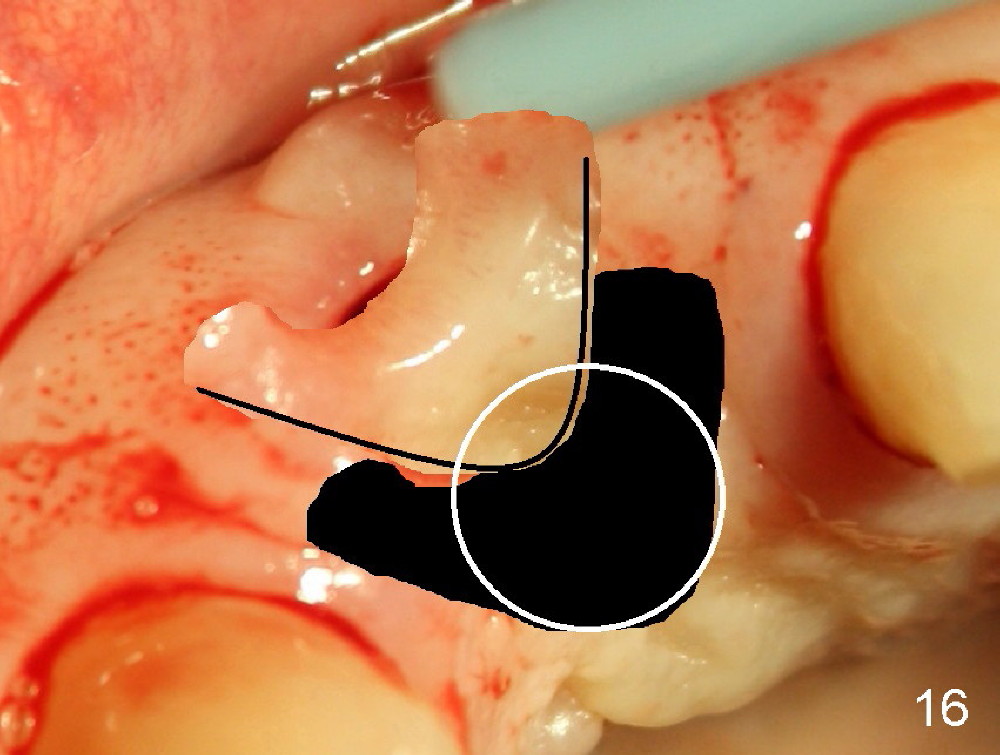

If a larger incision were made (Fig.14) and the flap were dissected freely (Fig.15), the buccal tissue deficiency would be less (Fig.16). Follow up is shown 2 3.